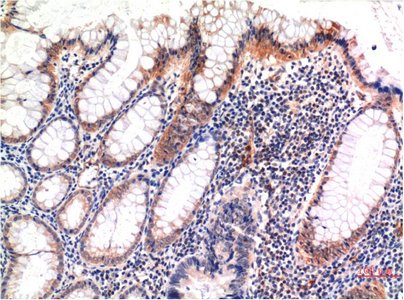

Main InformationTargetMLKLHost SpeciesMouseReactivityHumanApplicationsIF, IHCMW54kD (Observed)Conjugate/ModificationPhosphoDetailed InformationRecommended Dilution RatioIF 1:50-200; IHC 1:100-200FormulationLiquid in PBS containing 50% glycerol, 0.5% BSA and 0.02% sodium azide.Specificityphospho-MLKL (S358) protein detects endogenous levels of MLKLPurificationThe antibody was affinity-purified from mouse ascites by affinity-chromatography using specific immunogen.Storage-15°C to -25°C/1 year(Do not lower than -25°C)Concentration1 mg/mlMW(Observed)54kDModificationPhosphoClonalityMonoclonalClone Number6F8Antigen&Target InformationImmunogen:Synthetic Peptide of phospho-MLKL (S358)Specificity:phospho-MLKL (S358) protein detects endogenous levels of MLKLGene Name:MLKLProtein Name:MLKLOther Name:MLKLBackground:This gene belongs to the protein kinase superfamily. The encoded protein contains a protein kinase-like domain; however, is thought to be inactive because it lacks several residues required for activity. This protein plays a critical role in tumor necrosis factor (TNF)-induced necroptosis, a programmed cell death process, via interaction with receptor-interacting protein 3 (RIP3), which is a key signaling molecule in necroptosis pathway. Inhibitor studies and knockdown of this gene inhibited TNF-induced necrosis. High levels of this protein and RIP3 are associated with inflammatory bowel disease in children. Alternatively spliced transcript variants have been described for this gene. [provided by RefSeq, Sep 2015],Function:Domain:The protein kinase domain is predicted to be catalytically inactive.,similarity:Belongs to the protein kinase superfamily.,similarity:Contains 1 protein kinase domain.,Cellular Localization:Cytoplasm . Cell membrane . Nucleus . Localizes to the cytoplasm and translocates to the plasma membrane on necroptosis induction (PubMed:24316671). Localizes to the nucleus in response to orthomyxoviruses infection (By similarity). .Tissue Expression:Chondrocyte,Leukocyte,Lymph node,Research Areas:>>Necroptosis ; >>TNF signaling pathway ; >>Salmonella infection